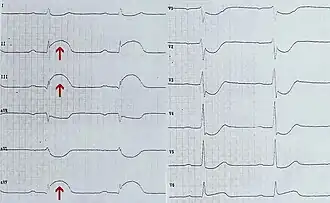

- Электрокардиограмма (ЭКГ) — метод предполагает запись активности сердца: насколько быстро оно бьётся и стабилен ли ритм. ЭКГ основана на регистрации силы и времени прохождения электрических сигналов через сердце. ЭКГ может указать на повреждения сердца, вызванные ишемической болезнью сердца, а также на текущий или перенесённый сердечный приступ. ЭКГ не используют для скрининга болезней сердца у людей с низким риском их развития[20].